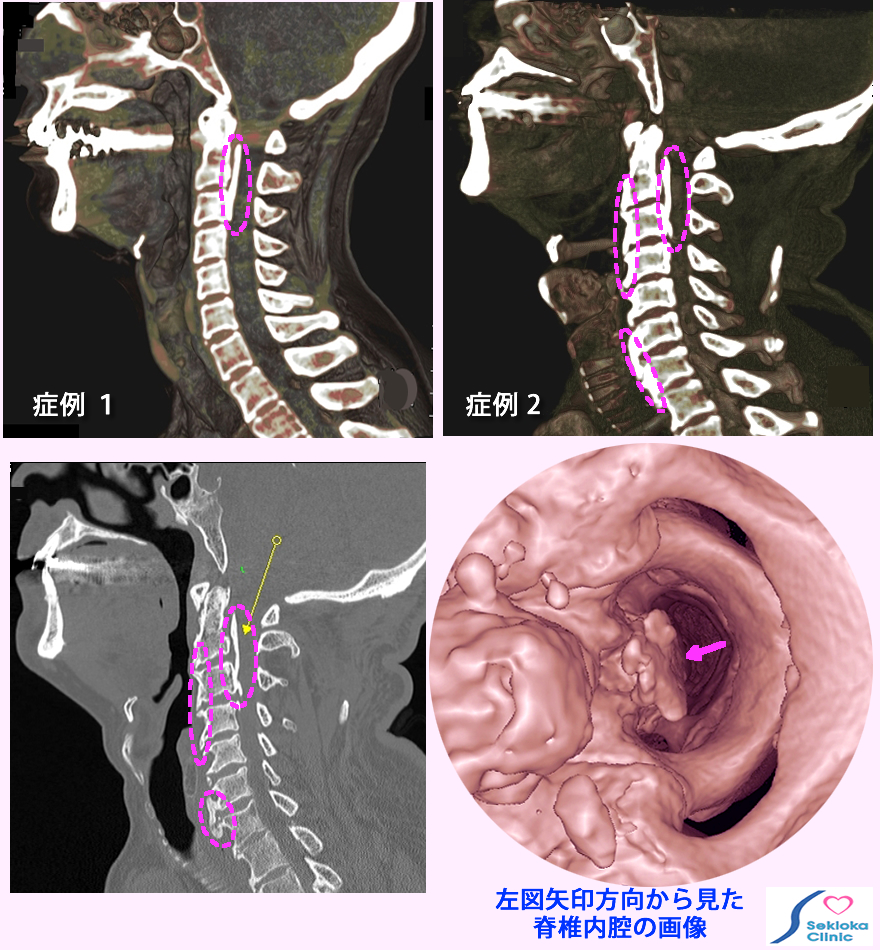

| 診断 | CT、MDCT、MRIで検査。MDCTは任意断面の画像で3次元的に観察できるので CTより正確な診断が可能。下図左は頚椎の側面方向の断面画像。症例1(左画像)は後縦靭帯の石灰化(骨のように硬くなる)を認め、脊椎内腔の神経が通る空間は狭くなっている。症例2 (右画像)は 後縦靭帯の骨化に加え前縦靭帯の骨化も認めた糖尿病の症例です。 |